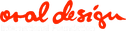

Peter Vryonis

オーストラリア開業

Peter Vryonisのキャスタブル・テクニック

キャスタブル・セラミックスのクラウンの臨床例から。